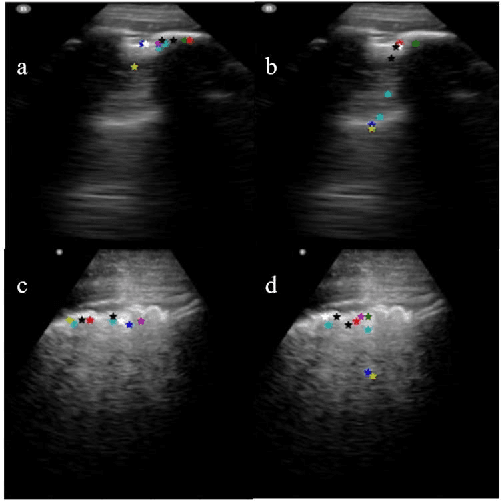

Abstract:Lung ultrasound (LUS) is an increasingly popular diagnostic imaging modality for continuous and periodic monitoring of lung infection, given its advantages of non-invasiveness, non-ionizing nature, portability and easy disinfection. The major landmarks assessed by clinicians for triaging using LUS are pleura, A and B lines. There have been many efforts for the automatic detection of these landmarks. However, restricting to a few pre-defined landmarks may not reveal the actual imaging biomarkers particularly in case of new pathologies like COVID-19. Rather, the identification of key landmarks should be driven by data given the availability of a plethora of neural network algorithms. This work is a first of its kind attempt towards unsupervised detection of the key LUS landmarks in LUS videos of COVID-19 subjects during various stages of infection. We adapted the relatively newer approach of transporter neural networks to automatically mark and track pleura, A and B lines based on their periodic motion and relatively stable appearance in the videos. Initial results on unsupervised pleura detection show an accuracy of 91.8% employing 1081 LUS video frames.